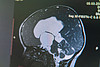

В Кировскую областную детскую клиническую больницу 1,5 годовалый пациент был госпитализирован с признаками прогрессирующей гидроцефалии. Мама малыша отметила, что ребенок стал беспокойный, увеличился объем головы, нарушилась походка. При проведении компьютерной томографии специалисты установили, что причиной ухудшающегося состояния была киста головного мозга, расположенная в третьем желудочке.

– Эта область находится в самой глубине головного мозга и имеет большое функциональное значение. Проводить операции на данном участке достаточно сложно, но в нашем арсенале есть инструменты толщиной всего 2 миллиметра, которые позволяют малоинвазивно проникнуть в самые глубокие отделы мозга, – рассказал врач-нейрохирург Кировской областной детской клинической больницы Эдуард Сырчин. – Именно благодаря этому современному оборудованию мы провели нашему маленькому пациенту эндоскопическую перфорацию дна третьего желудочка. В рамках оперативного вмешательства через отверстие диаметром в полсантиметра нам удалось удалить кисту и сформировать новые пути оттока ликвора.